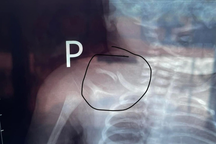

Ngay khi tiếp nhận bệnh nhân, các bác sĩ đã thăm khám, chỉ định chụp X-quang và các xét nghiệm cần thiết.

Bé gái bị nhiều vết bầm tím khắp người, may mắn không bị tổn thương tới xương (Ảnh: Bộ Công an).

"May mắn, bé gái không bị gãy xương, không có tổn thương nội tạng nguy hiểm, nhưng toàn thân nhiều vết bầm dập phần mềm, cho thấy cháu đã phải chịu lực tác động mạnh và liên tục”, BS Dung thông tin.